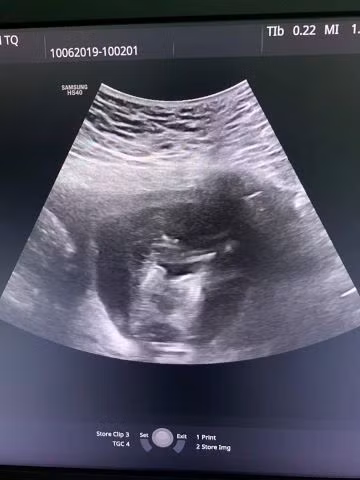

Mới đây, khoa Khám bệnh - Bệnh viện đa khoa tỉnh Tuyên Quang đã tiếp nhận một trường hợp thai phụ mang thai đôi đặc biệt, đó là chị Trần Thị Thu P., 21 tuổi, trú tại huyện Yên Sơn, Tuyên Quang.

Chị P. mang thai lần đầu, có thai tự nhiên. Kết quả khám thai của chị P. cho thấy, hiện tại chị đang mangthai đôi ở tuần thứ 12 và điều đặc biệt là 2 thai dính nhau từ phần ngực xuống đến phần bụng, có chung một quả tim và cả 2 thai đều có tăng khoảng sáng sau gáy (2,5mm và 8,0mm).

Ths.Bs Dương Văn Chương - khoa Phụ Sản, Bệnh viện đa khoa tỉnh Tuyên Quang (người trực tiếp thăm khám cho chị P.) cho biết: Đây là trường hợp song thai hiếm gặp, chiếm khoảng 1% song thai một noãn trong khi tỷ lệ chung của song thai một noãn là 3 - 5/1000 ca đẻ.

Trên thế giới đã có nhiều trường hợp song thai dính nhau được đẻ ra và phẫu thuật gỡ dính thành công, nhưng với trường hợp của chị P. thì tiên lượng không tốt vì thứ nhất hiện tại một trong hai thai đã có hiện tượng phù và có nguy cơ chết lưu; thứ hai vì hai thai dính nhau cả phần ngực - bụng và chung nhau một quả tim nên khả năng phẫu thuật tách rời sau sinh là vô cùng khó khăn.